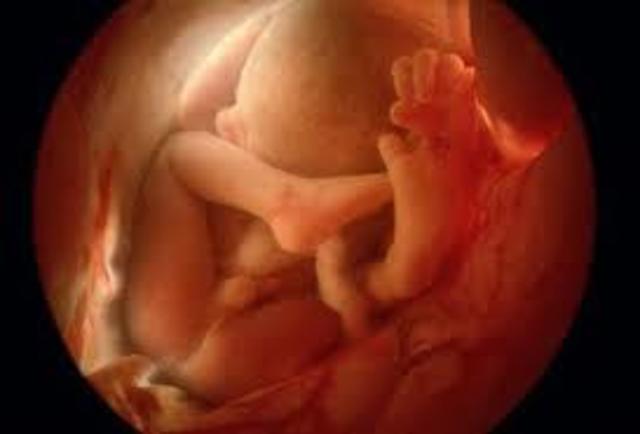

• Embrionaria

Embrionaria

Se comprende desde la cuarta semana hasta la octava. El embrión adquieresu forma casi definida y desarrolla la mayor parte de sus órganos.

• 6ta Semana

6ta Semana

Se empiezan a forrmar los parpados, se pueden reconocer los brazos y antebrazos

• 7ta Semana

7ta Semana

La cabeza sigue sieno voluminosa, aparecen los ezbosos de los dedos de la mano y del pie. Comienza a diferenciarse el sexp